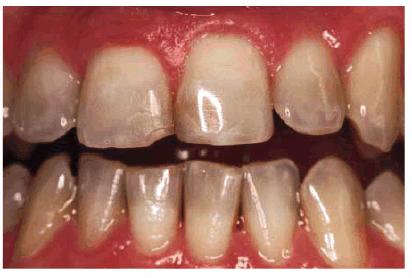

smile (Figur 323s1823d es 18-1A, and 18-1B). Decades ago, the full crown

Figur 323s1823d e 18-1A: This 21-year-old girl had chipped her anterior incisors when she was a teenager.

Figur 323s1823d e 18-1B: Cosmetic contouring was the most conservative treatment available and was performed in a less than 1-hour appointment.